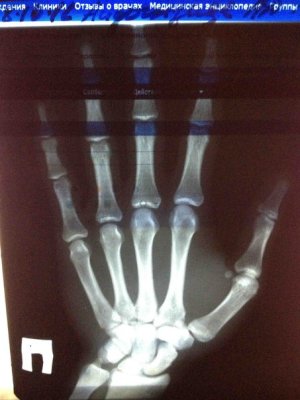

Зоны роста

Зоны роста закрыты! У Вас нормальный рост. СТГ от лукавого, он может только сделать Вас инвалидом.